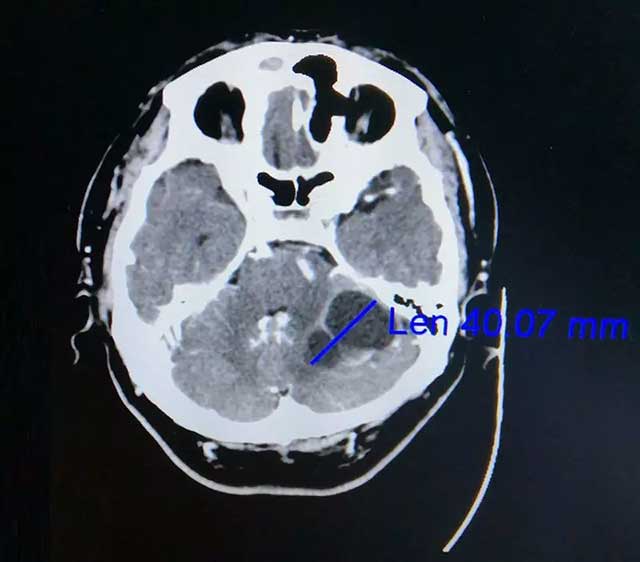

在家人陪伴下,劭阿伯到醫(yī)院做了檢查。查頭顱CT提示:左側(cè)小腦囊實(shí)性占位,很可能是轉(zhuǎn)移瘤。后又經(jīng)PET-CT檢查提示:左側(cè)小腦半球不規(guī)則囊性占位,轉(zhuǎn)移可能性大,原發(fā)腫瘤待排。此時(shí)懸在劭阿伯心中的“達(dá)摩克利斯之劍”搖搖欲墜,原來(lái)兩年前劭阿伯曾患肺癌,接受過(guò)放化療。為尋求進(jìn)一步治療,劭阿伯一家慕名來(lái)到上海藍(lán)十字腦科醫(yī)院。

▲ 增強(qiáng)CT顯示腫瘤達(dá)4公分大小

在查體時(shí),劭阿伯雙側(cè)指鼻試驗(yàn)略遲緩、欠穩(wěn)定,雙側(cè)跟膝脛實(shí)驗(yàn)略欠穩(wěn)定,閉目難立征不合作。一般來(lái)說(shuō),指鼻動(dòng)作笨拙、不準(zhǔn)確、不協(xié)調(diào)、不平穩(wěn)說(shuō)明病側(cè)上肢共濟(jì)失調(diào),提示小腦半球的病變;颊哂忻鞔_肺癌病史,根據(jù)影像學(xué)表現(xiàn)考慮為:肺癌左側(cè)小腦轉(zhuǎn)移。